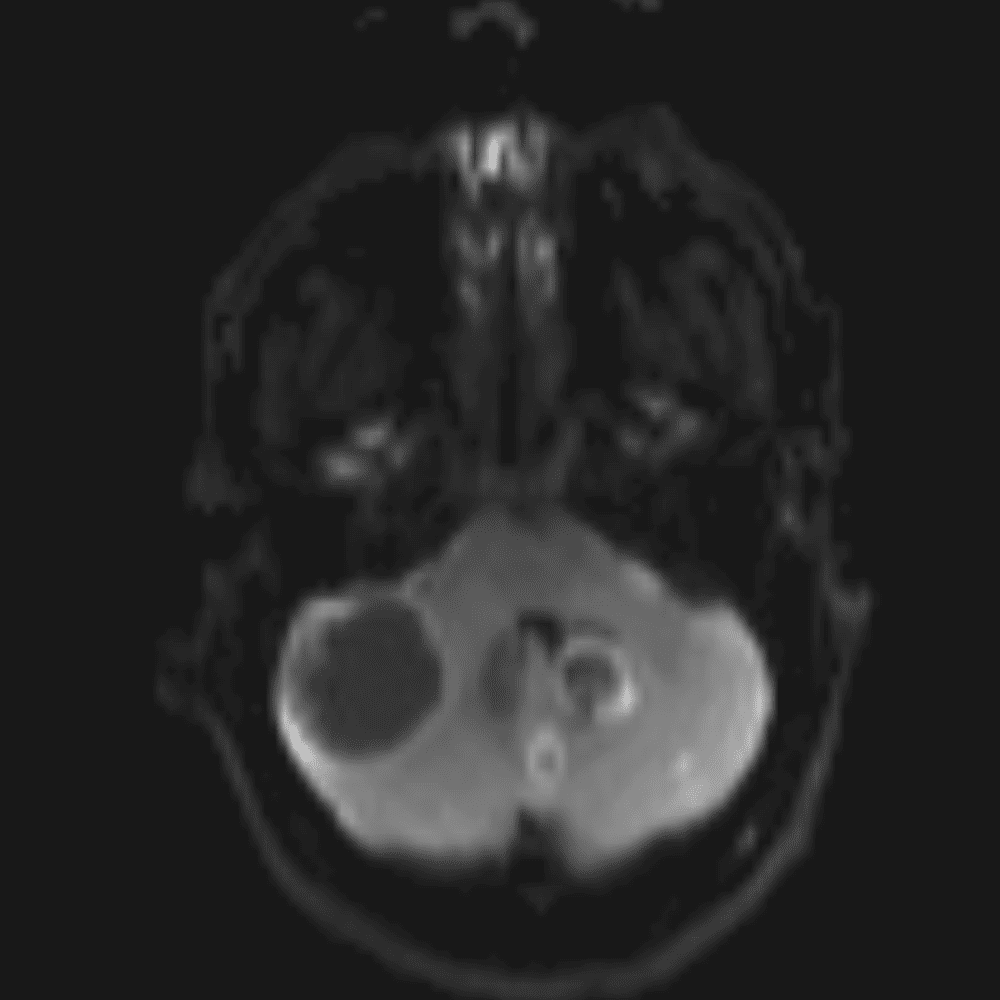

๋‹น์ง ์‹œ ํ”ํžˆ ๋ณผ ์ˆ˜ ์žˆ๋Š” ์‚ฌ๋ก€์˜ ์ „ํ˜•์ ์ธ ์˜ˆ๋ฅผ ํฌํ•จํ•ฉ๋‹ˆ๋‹ค.

39 ์‚ฌ๋ก€

์—ฐ์Šต

๋ฏธ๋ฌ˜ํ•˜๊ฑฐ๋‚˜ ์–ด๋ ค์šด ์‚ฌ๋ก€์™€ ์ผ๋ถ€ ์ •์ƒ ์‚ฌ๋ก€๋ฅผ ํฌํ•จํ•˜์—ฌ ๋‹น์ง์„ ์‹œ๋ฎฌ๋ ˆ์ด์…˜ํ•ฉ๋‹ˆ๋‹ค.

50 ์‚ฌ๋ก€